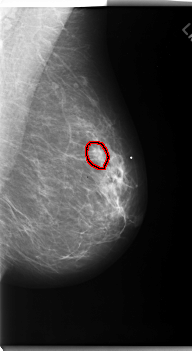

C_0170_1.RIGHT_MLO

FILE: C_0170_1.LEFT_MLO.OVERLAY

TOTAL_ABNORMALITIES 1

ABNORMALITY 1

LESION_TYPE MASS SHAPE OVAL MARGINS SPICULATED

ASSESSMENT 5

SUBTLETY 4

PATHOLOGY MALIGNANT

TOTAL_OUTLINES 1

BOUNDARY